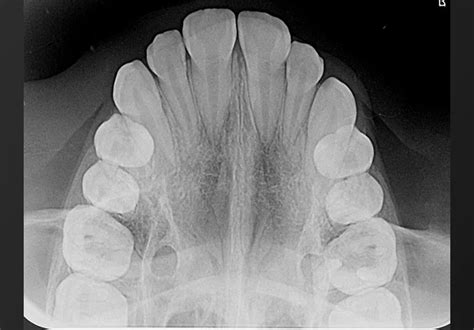

Figura 4 Ortopantomografía pretratamiento.

La ortopantomografía inicial (fig. 4) muestra una dentición mixta, iniciando el segundo período de recambio, con obturaciones a nivel de 16 y 26 y cóndilos mandibulares simétricos.